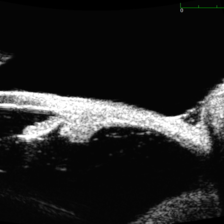

Large, Dome-Shaped Peripheral Choroidal Melanoma - UBM

Large, Dome-Shaped Peripheral Choroidal Melanoma - UBM

Feb 13 2020 by Michael Seider, MD

Large, dome-shaped peripheral choroidal melanoma of the left eye with inferior exudative retinal detachment. Note the lack of obvious orange pigment over the tumor and apparent drusen anteriorly. A lack of ophthalmoscopically obvious lipofuscin is not uncommon among larger choroidal melanomas. B-Scan ultrasonography (transverse, 10 o’clock) confirms a low-moderate internally reflective dome-shaped choroidal lesion with a small adjacent retinal detachment. Ultrasound biomicroscopy (radial, 10 o’clock) confirms no ciliary body involvement of the tumor.